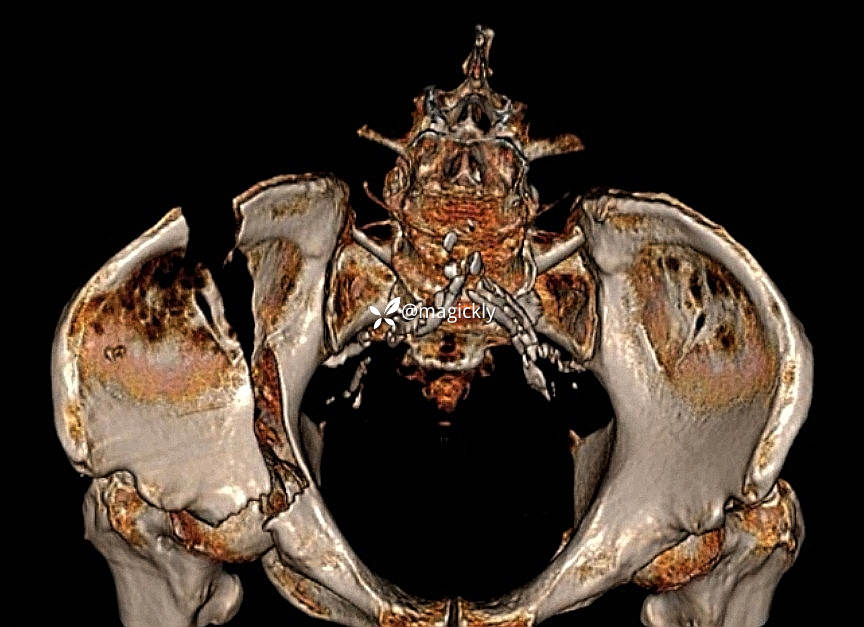

【检查】:局部体征明确,影像学结果如下

【临床诊断】:髋臼骨折(后上壁)